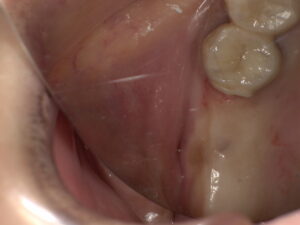

術前です。

切開をした状態です。ここまで1分くらいです。